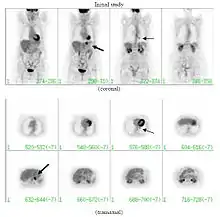

PET scan

If there is an intermediate risk of malignancy, further imaging with positron emission tomography (PET scan) is appropriate (if available). It can be done simultaneously as a CT scan in the form of PET-CT. Around 95% of patients with a malignant nodule will have an abnormal PET scan, while around 78% of patients with a benign nodule will look normal on PET (this is the test sensitivity and specificity).[15] Thus, an abnormal PET scan will reliably pick up cancer, but several other types of nodules (inflammatory or infectious, for example) will also show up on a PET scan. If the nodule has a diameter of less than one centimeter, PET scans are often avoided because of an increased risk of falsely normal results.[15][16][17] Cancerous lesions usually have a high metabolism on PET, as demonstrated by their high uptake of FDG (a radioactive sugar).

PET-CT of a tuberculoma.